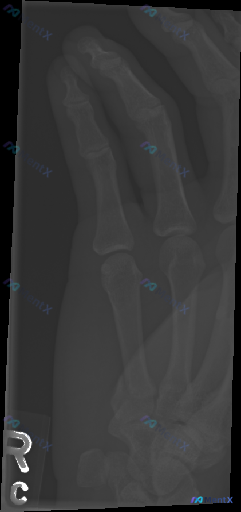

整理了一份右手指部的影像+临床分析资料,觉得很适合讨论「影像阴性≠临床没事」的情况。 先给出影像的客观结论: 这份是右手指斜位X光片,影像科报告的描述是: - 各段骨皮质连续,未见明显骨折线或脱位征象 - 关节对位正常,关节间隙清晰 - 骨质密度均匀,未见骨侵蚀或增生 - 软组织轮廓自然,未见明显高...